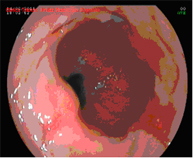

Radiofrecuencia con sistema HALO

El sistema Halo de radiofrecuencia es un aparato que permite la ablación de la mucosa esofágica hasta una profundidad de 1 mm de forma segura y uniforme. La ablación es una técnica en la que se calienta el tejido hasta que deja de ser viable o estar vivo. La tecnología HALO es un tipo muy específico de ablación en la que la energía calorífica se aplica de forma precisa y controlada. Los ensayos clínicos han demostrado que el tejido de Barrett se puede eliminar completamente con la tecnología de ablación HALO en el 98,4% de los pacientes.

Hay que hacer un seguimiento endoscópico y es probable que sea necesario repetir el tratamiento una o dos sesiones.